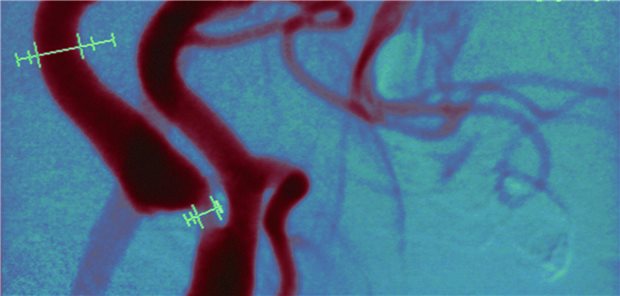

Stumme Karotisstenose: Lohnt sich die Revaskularisation?

Eine schwierige Entscheidung

Empfehlungen eines Gefäßmediziners

Welche Patienten mit asymptomatischer Carotis-Stenose operiert werden sollten